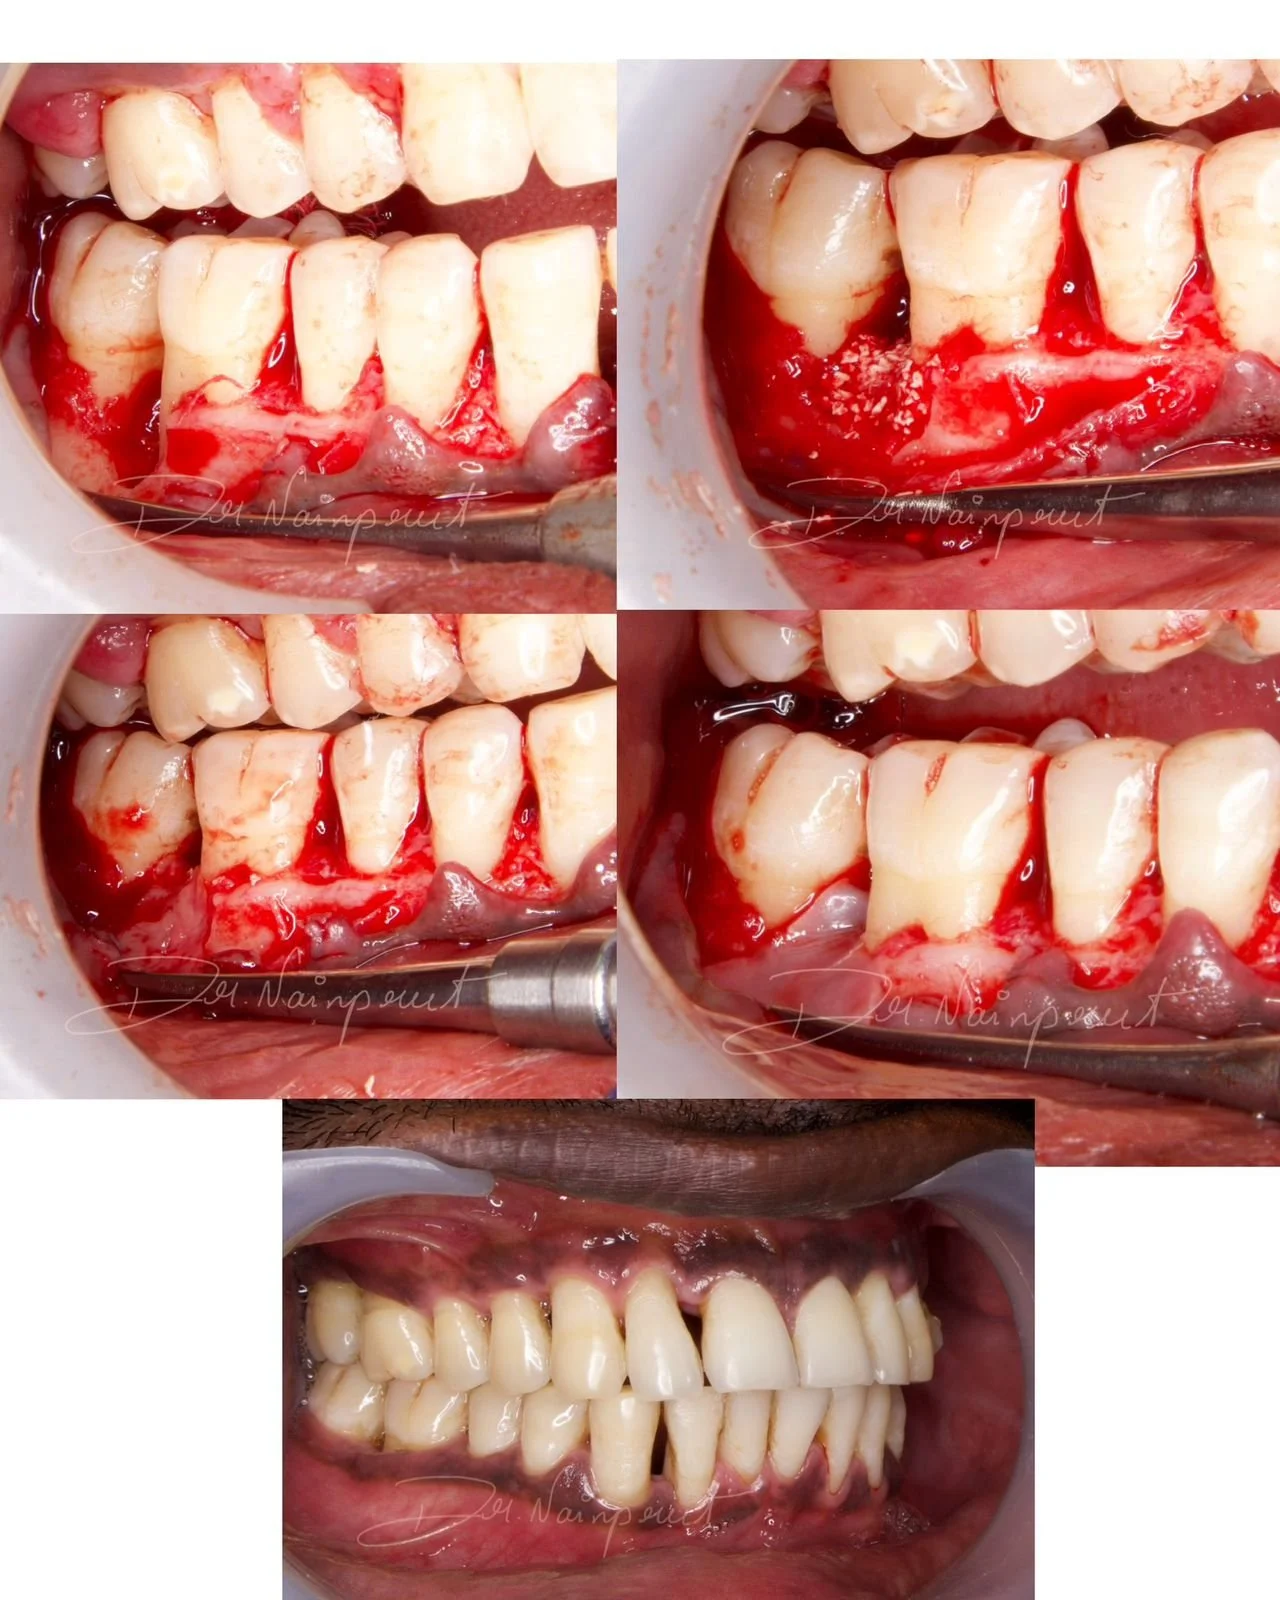

ROOT COVERAGE WITH CORONALLY ADVANCED FLAP

Surgery performed by Dr Poulami

Periodontics SaveethaSeptember 8, 2024